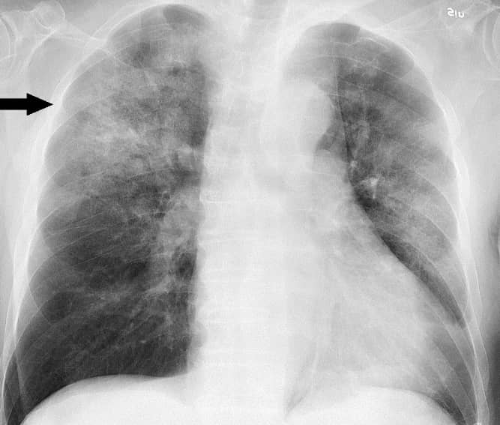

폐렴은 세균, 바이러스, 곰팡이 등 다양한 미생물에 의해 폐에 염증이 발생하는 질환입니다. 이 질환은 기본적으로 폐의 공기주머니에 생긴 염증을 중심으로 발생합니다.

폐렴은 폐의 염증을 동반하는 질병으로, 이에 따라 다양한 임상 증상이 발생합니다. 대표적으로 호흡 곤란, 기침 및 가래의 증가가 관찰됩니다. 특히, 가래의 색상 변화, 예를 들어 노란색 또는 뿌옇게 보이는 경우는 주의가 필요합니다.